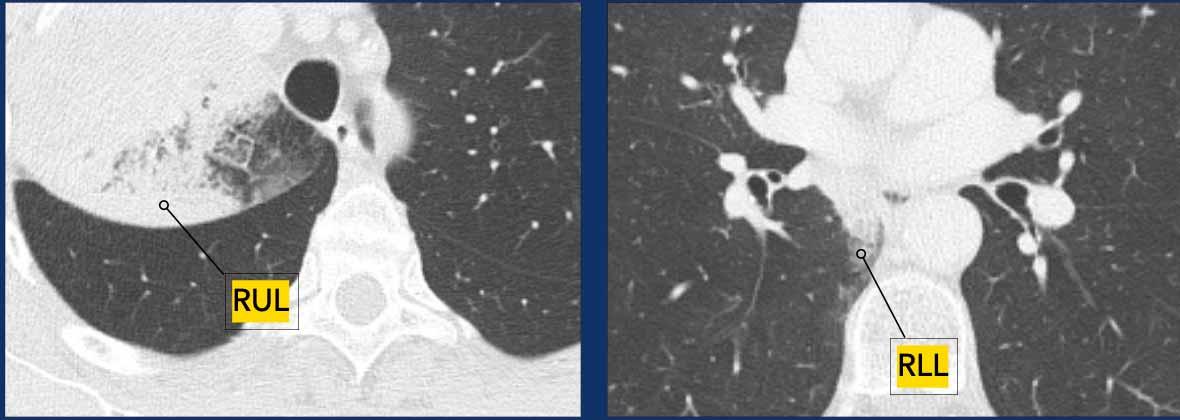

2. Các nốt khối u riêng biệt cùng loại ác tính

- T3: Nếu các nốt nằm trong cùng một thùy.

- T4: Nếu các nốt nằm cùng bên nhưng ở các thùy khác nhau.

- M1a: Nếu các nốt nằm ở thùy phổi đối bên.

- Một phân loại N và M duy nhất được áp dụng cho tất cả các nốt.

Ví dụ:

- T3N2aM0 ở thùy trên phổi phải (RUL), với phân loại T3 dựa trên nốt riêng biệt trong cùng thùy.

3. Tổn thương kính mờ hoặc dạng lepidic đa ổ

- Giai đoạn T được xác định bởi tổn thương chiếm ưu thế nhất.

- Một phân loại N và M duy nhất được áp dụng cho tất cả các tổn thương.

- Tính đa ổ được ký hiệu là (#/m), ví dụ ba tổn thương được ký hiệu là 3/m.

- T1aN0M0 (2/m), với phân loại T1a dựa trên tổn thương chiếm ưu thế ở thùy dưới phổi phải (RLL).